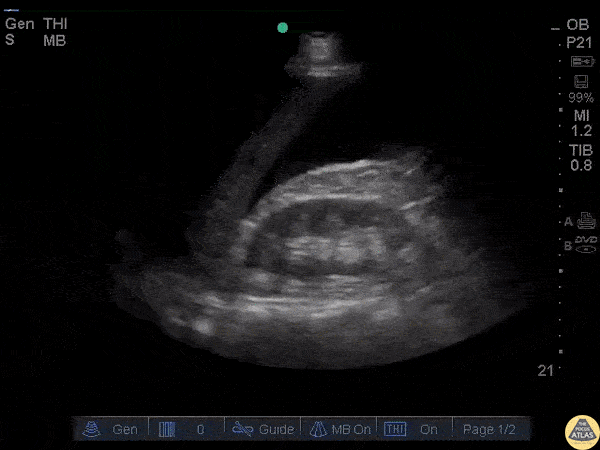

Trauma - RUQ Free Fluid

A patient presented with LUQ trauma but the perisplenic window was negative for free fluid. Morison’s pouch was positive for free fluid emphasizing the importance of scanning all regions for free fluid in trauma. Image courtesy of Robert Jones DO, FACEP @RJonesSonoEM Director, Emergency Ultrasound; MetroHealth Medical Center; Professor, Case Western Reserve Medical School, Cleveland, OH View his original post here